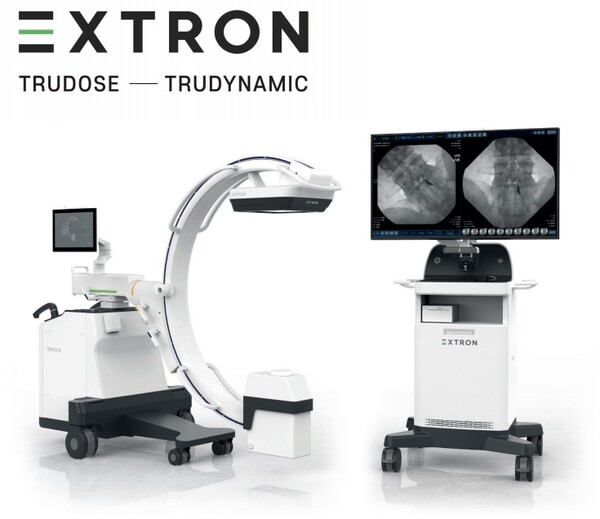

Sistema de Rayos X

Arco en C Digital

Línea Premium para uso en Cirugía General y aplicaciones Vasculares.

Este Sistema genera imágenes sin distorsiones, de alta resolución y con bajo ruido para ayudar al personal médico a diagnosticar y realizar procedimientos de precisión.

EXTRON maximiza la comodidad del usuario, con un monitor panorámico 4K de 43”.